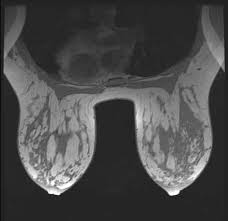

Advanced Radiology Consultants Fast Breast Mri from www.adrad.com The term tomography comes from the greek words tomos (a cut, a slice, or a section) and graphein (to write or record). They may also use it to learn more about the cancer after they find it. If i had contrast on the earlier ct, my cancer would have been found 2 1/2 years earlier. When a ct scan misses cancer. Breast cancer affects over 200,000 women each year. If you have a large breast cancer, your doctor may order a ct scan to assess whether or not the cancer has moved into the chest wall. A ct scan may be used to: Therefore, ct scans can lead to a false negative this can negatively impact your ability to get any treatment at all this can prolong the time it takes you to access treatment

95% of nodules found are benign. Learn the stage of your cancer. Long story short i have a ct scan with contrast on 1st june to look for cancer in the abdominal cavity. Doctors use a computed tomography (ct) scan, also called a cat scan, to find cancer. The scan is painless and takes about 10 to 30 minutes. Other names for this test: In general breast cancer can be detected on a routine chest ct scan regardless of if contrast media is used or not. Learn more about it on our blog. The term tomography comes from the greek words tomos (a cut, a slice, or a section) and graphein (to write or record). Amongst everything that's been going on i have not been checking my breasts, stupidly i was looking for cancer in other areas and now i think my breast may be the culprit. The scan is painless and usually takes between 5 to 30 minutes. Are you preparing to have this procedure soon? Before the scan, you will either drink a liquid dye or be given an injection of dye into a vein in your arm.